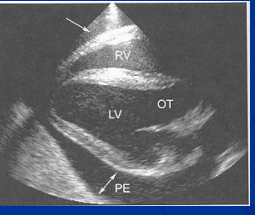

Pericarditis in horses

Et: Inflam of pericardium, Actinobacillus, Strep zoo, influenza, EVA, AHS

Fibrinous or Effusive

Cs: fever, depression, exercise intolerance, weakness, tachycardia, muffled heart sounds, weak pulses, circulatory collapse

Dt: Echo (effusion), Pericardial tap, ECG w/ Low QRS amp

Tx: Pericardial drainage + lavage, Antibiotics, Corticosteroids

Prognosis poor